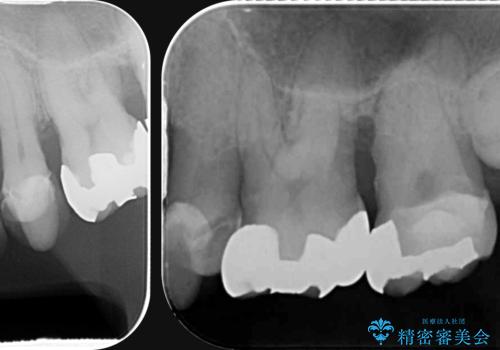

インプラント・ブリッジ補綴を含む、歯周病全顎治療

- 歯が全体的に揺れ始め、恐怖を感じ他院に相談に行ったところ、全体的な歯周病の問題・抜歯の必要性・入れ歯の提案を受け、入れ歯以外の選択肢を希望され来院されました。

全体的な歯周病検査を行い、多数の残すことのできない抜歯の必要な歯を認めたため、残せる歯に対しての徹底的な歯周病治療、失った歯に対しブリッジ・インプラント治療を全顎的に行っていくこととしました。